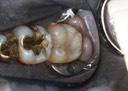

Joe Cha #3 prep